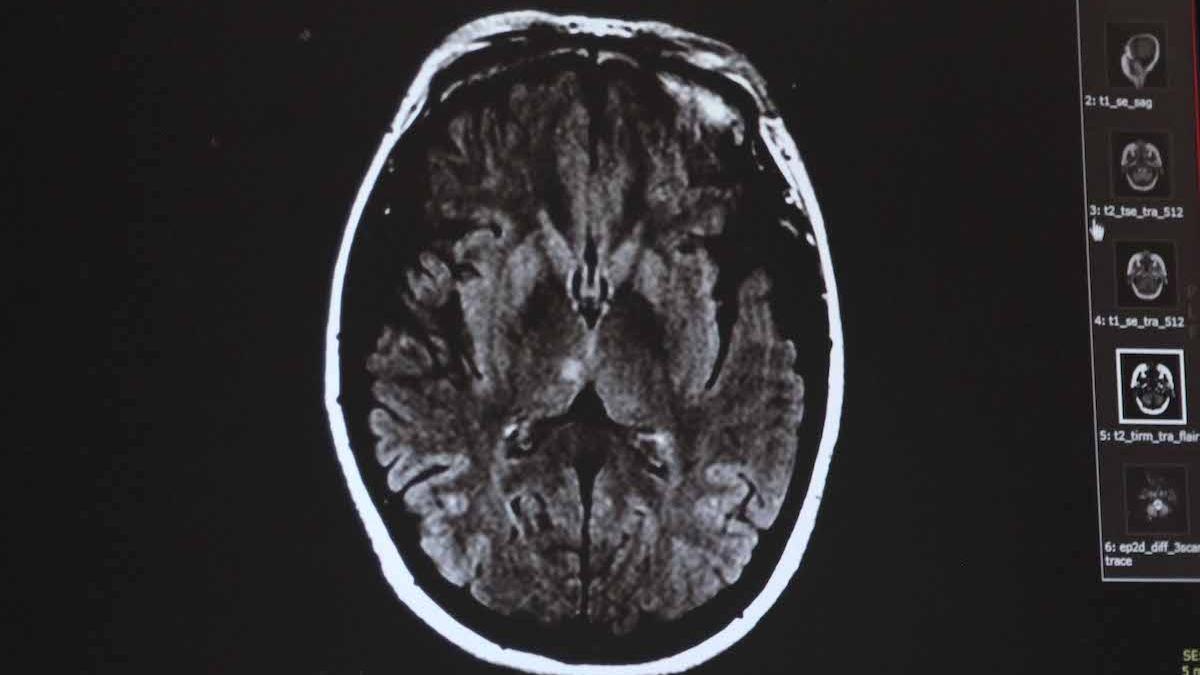

Kim Kardashian dezvăluie că a fost diagnosticată cu anevrism cerebral. Ce i-au spus medicii şi care sunt simptomele 24 Oct

Oamenii de știință au inventat nanoroboți care pot repara anevrismele cerebrale. Cum funcționează noua tehnologie06 Sep

Avertismentul unui renumit neurolog. Care este motivul unei dureri de cap puternice care apare brusc 11 Ian